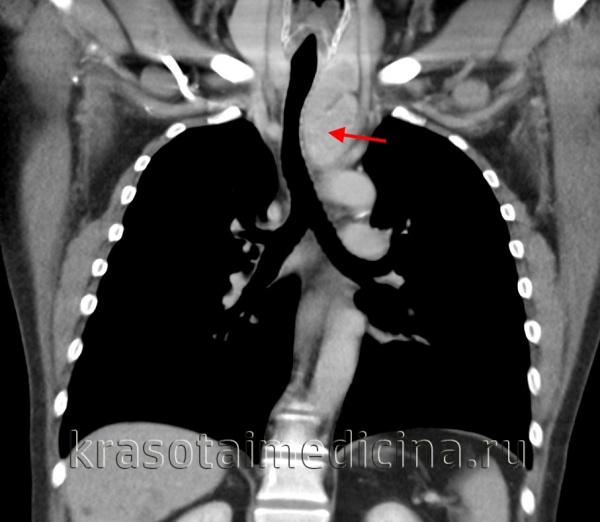

(а) У пациента с параганглиомой в средостении при КТ с контрастным усилением в области бифуркации трахеи определяется объемное образование, сдавливающее правую легочную артерию и накапливающее контрастное вещество. В грудной клетке параганглиомы чаще всего формируются вдоль симпатического ствола, блуждающего нерва или в сердце.

(б) У этого же пациента при МРА в кососагиттальной проекции визуализируется объемное образование, контрастирующееся немного гетерогенно. Интенсивное контрастирование при введении гадолиния является характерным признаком параганглиомы.